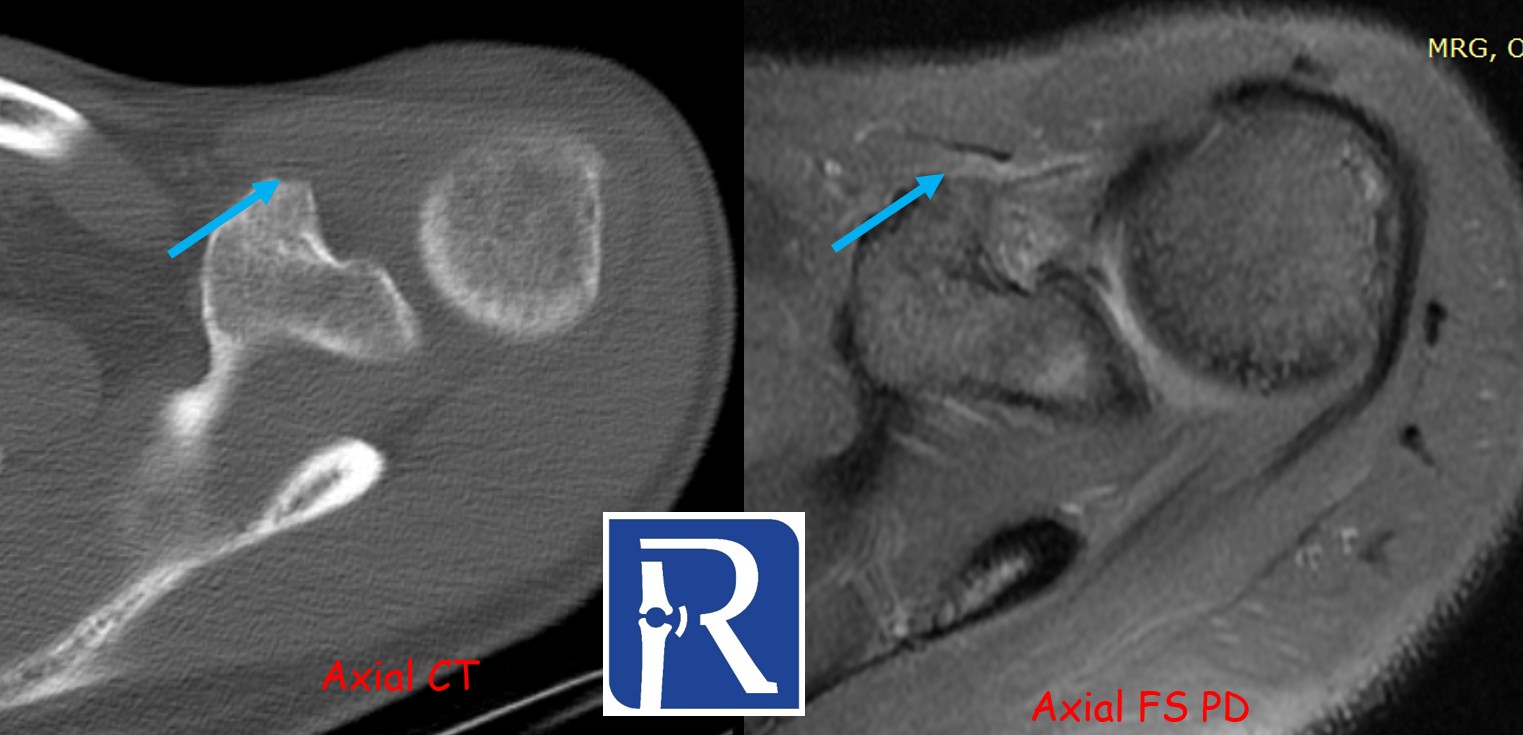

CT Findings:

CT demonstrates a bony defect at the coracoid process (blue arrows) and shows that the resected bone fragment has been fixed to the inferior glenoid defect with two anchors (white arrows). These findings are consistent with a Latarjet procedure.

A radiolucent anchor is also identified at the superior glenoid, corresponding to the site of the labral repair (red arrows).